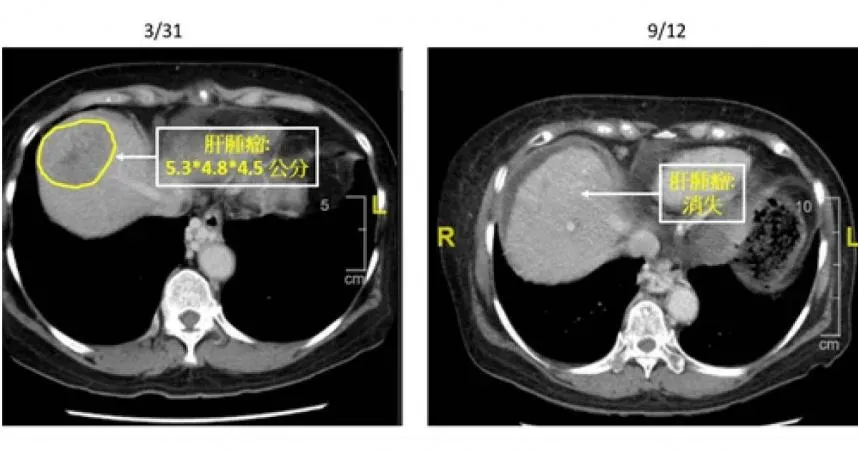

肝炎

肝硬化

肝癌